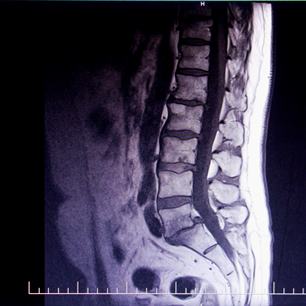

Assicurazioni Generali. Tak tudy vcházel do háku Franz K. Pracovní doba od 8 do 18 hod. s dvouhodinovou přestávkou v poledne. Jednou za dva roky o 14 dní dovolené. Ústav měl právo bez nároku na zvláštní odměnu nařídit i práci mimo stanovenou pracovní dobu. Nevydržel tam ani rok. A snímek z MR, kde je zakopaný pes?